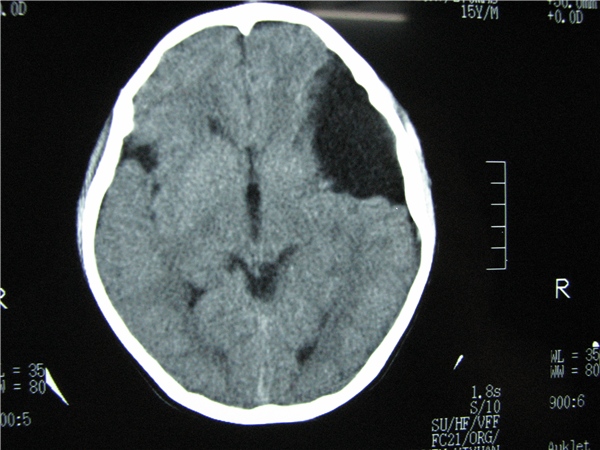

标题: CT20748:M 15Y 头痛,以前有外伤史请老师看看除了囊肿还有别 [打印本页]

标题: CT20748:M 15Y 头痛,以前有外伤史请老师看看除了囊肿还有别

m 15y 头痛,以前有外伤史请老师看看除了囊肿还有别的吗?

蛛网膜囊肿。眼拙,看不出别的,倒是看到了双侧大脑中动脉影,类似“致密动脉征”。

双侧侧裂池和纵裂池近前颅窝蛛网膜囊肿。

不能除外脑穿通畸形

无明显占位及负占位效应,考虑软化灶并脑室穿通畸形囊肿、局限性脑萎缩

蛛网膜囊肿,不能除外脑穿通畸形,支持。